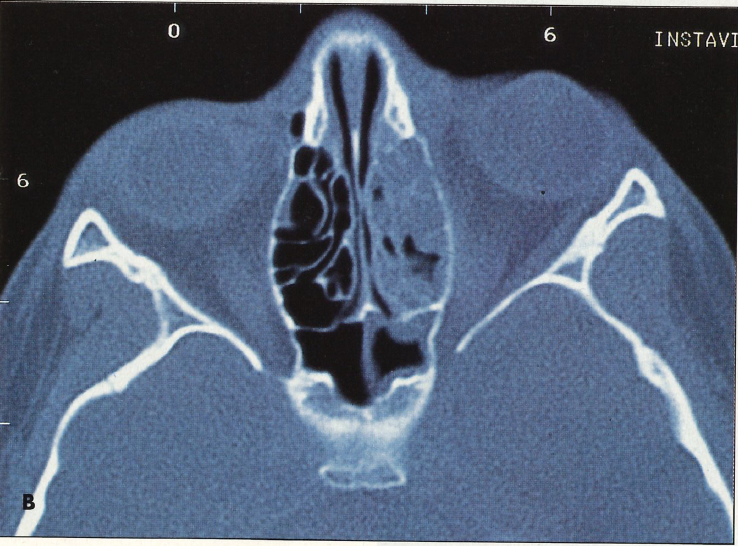

High-resolution CT scans, including axial and coronal views (Figures A and B), are imperative. MRI may help define orbital abscesses and evaluate the possibility of cavernous disease. Consultation with specialists in infectious disease, ophthalmology, or otolaryngology is recommended.

Figures. The coronal (A) and axial (B) CT scans show opacification of the left maxillary sinus, interruption of the left lamina papyracea (lateral ethmoid wall), proptosis of the left eye, and inflammatory changes to the left orbit.